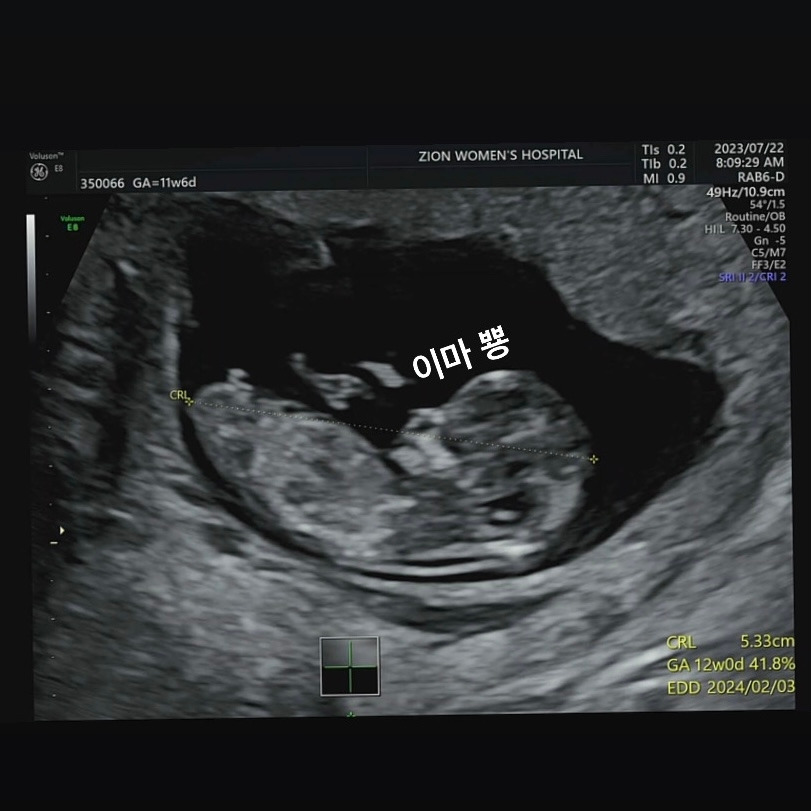

드디어 12주 차가 되었다. 오늘은 한 달 만에 병원 검진이 있는 날로, 1차 기형아 검사와 입체 초음파 검사를 하기로 한 날이다. 차차는 한 달 동안 얼마나 컸을까 두근두근하며 아침 일찍 병원으로 향했다. 오전 8시에 시작한 병원 검진은 친절하신 직원분들로 인해 매우 행복했다. 오늘 첫 손님으로 초음파 검진실에 들어섰다. 처음으로 배 쪽으로 초음파를 진행했다. 까만 화면이 밝아지며 무언가를 비추기 시작했다. 그리고 드디어 한 달 만에 보는 차차가 보였다. 내 눈엔 사람의 형체로 잘 보이지 않던 차차가 사람의 모습을 하고 있었다. 나와 남자친구 둘 다 너무 놀라 말이 사라졌다. 심장소리를 듣고, 입체초음파를 보고, 그리고 꼬물꼬물 실시간으로 움직임까지 보았다. 차차는 사람이었다.

그 외에도 내가 차차에 대해 더 크게 느낀 부분이 하나 있다. 바로 차차의 이마다. 현시점에서 가장 뚜렷한 인간의 면모를 보여주는 차차의 이마는 내 이마를 닮았더라. (자신할 수 있는 게, 내 남자친구의 이마는 납작한 편이다) 차차의 이마처럼 내 이마는 윗부분이 높게 솟은 둥근형이다. 이마에 대해 이야기하자마자 남자친구도 내 이마를 닮았다며 신기해했다. 차차에게서 유전적으로 나와 닮은 모습을 봐버리자, 이미 샘솟은 애정이 마구마구 솟구치기 시작했다. 이 아이를 어째야 할까? 손가락 만한 아이가 벌써 나를 닮아있다니. 아직 성별도 모르고 제대로 된 생김새도 모르는 차차에게 마음을 홀랑 뺏겨버렸다. 우리 인간도 동물로써 이렇게 프로그래밍되어 있는 거겠지, 외적인 요소를 유전시키며 나를 닮은 내 자손의 모습에서 안도감을 느끼고 애정을 쏟아 키우도록 되어있는 것이겠지. 어렸을 적 읽은 이기적 유전자의 내용을 비로소 실감하기 시작했다.